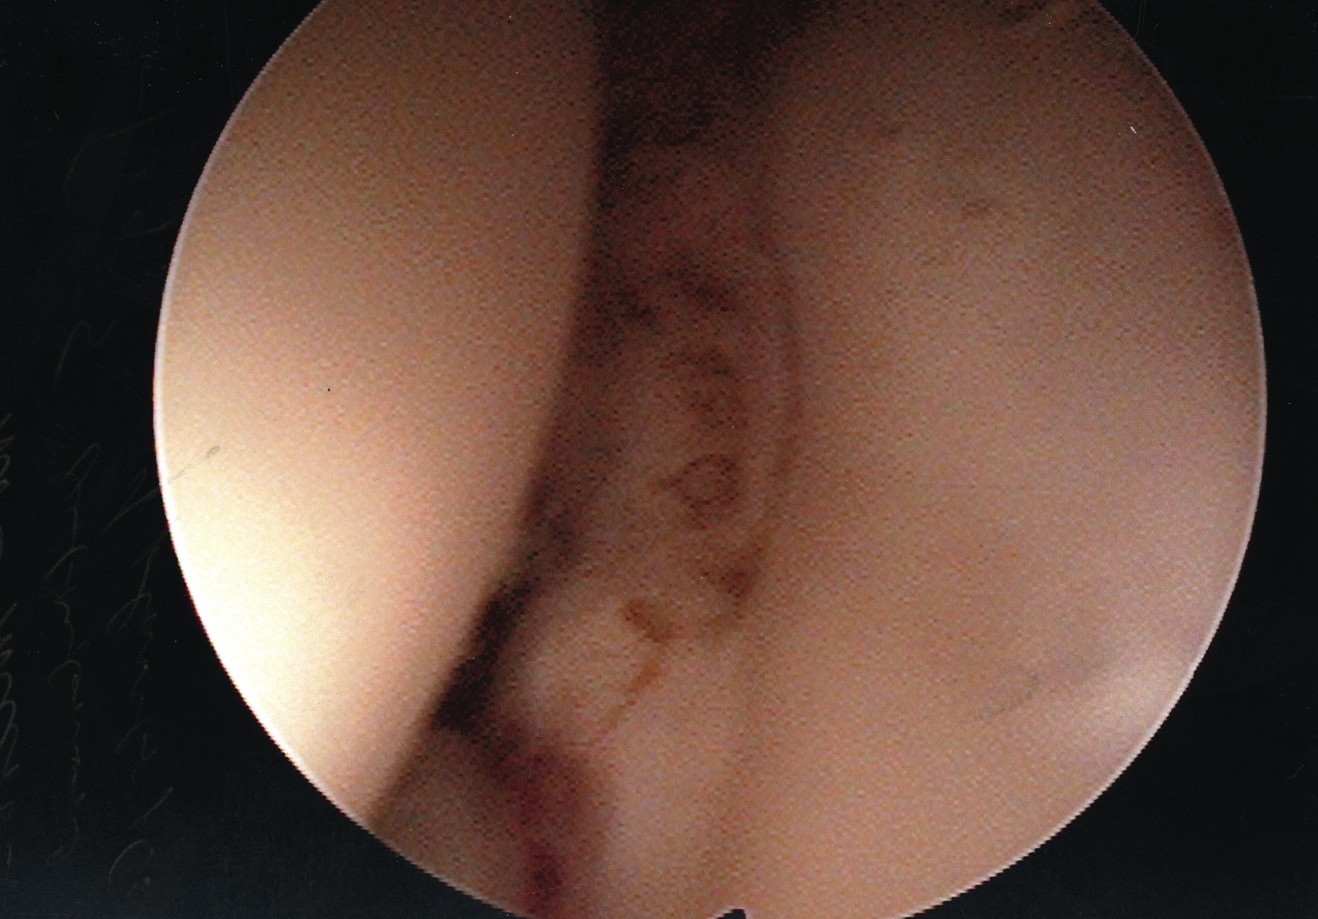

Accordingly, we recently undertook a study to evaluate the technical ease of using this approach to treat patients with plantar plate derangement, metatarsalgia and synovitis of the second metatarsophalangeal joint complex, and to assess early postoperative clinical findings. In regard to the surgical repair, we initially address the metatarsalgia, proceed to repair the plantar plate derangement and finally, using the radiofrequency-based device to ablate the synovitis affected tissue of the second metatarsophalangeal joint complex, we perform the microcapsulotomies of the plantar plate. To treat the plantar plate derangement, one makes an s-shaped incision from the distal third of the second metatarsal shaft and carries the incision to the base of the proximal phalanx. Then you would expose the superior aspect of the head and neck of the metatarsal via sharp dissection. Proceed to open and expose the dorsal aspect of the metatarsophalangeal joint. Then we perform a shortening Weil-type osteotomy of the second metatarsal.9,10 We perform the osteotomy from the dorsal distal aspect of the metatarsal and translate it toward the proximal plantar, just proximal to the plantar condyles and parallel to the plantar aspect of the foot. We adjusted the distal osteotomized capital fragment proximally (3 to 5 mm) to eliminate clinical prominence of the metatarsal head in the plantar position. We proceeded to fixate the osteotomy site with two 0.035 mm guide wires and secured it with either a 2.0 mm or a 2.4 mm compression screw. After decompression of the second metatarsophalangeal joint and internal fixation of the second metatarsal shaft, we applied gentle digital traction to distract and open up the second metatarsophalangeal joint complex. Using a 2.7 mm angled arthroscope, one can evaluate the joint to determine the extent of the synovitis. Following inspection, the surgeon can perform a synovectomy using the Topaz microdebrider device (ArthroCare) as directed by the manufacturer’s instructions. With continued digital traction, we examined the plantar capsular structures and plantar plate. We used the Topaz device to perform the microcapsulotomy procedure in the degenerated plantar plate. The purpose of this step is creating a low-grade inflammatory response necessary for stimulating a healing response in the degenerated tissue. For both ablation procedures, one can use the Topaz device at controller setting 4. For the microcapsulotomy, however, we used the system timer (set at 0.5 seconds) while making each microablation in order to specify a sufficient ablation. We created microablations over the affected tissue region to form a grid-like pattern. Every fourth microablation was slightly deeper in order to ensure adequate penetration of treatment. The affected plantar plate area usually required nine to 12 microablations. After concluding the microablation portion of the procedure, we irrigated the treated area and closed it in standard fashion. We subsequently repaired any associated contributory deformities, such as hallux adductovalgus and/or hammertoe deformity as appropriate. In regard to the radiofrequency-based portion of the procedure, it was slightly more challenging than surgical resection. However, it did offer the benefit of preserving the plantar plate and avoided a plantar incision.